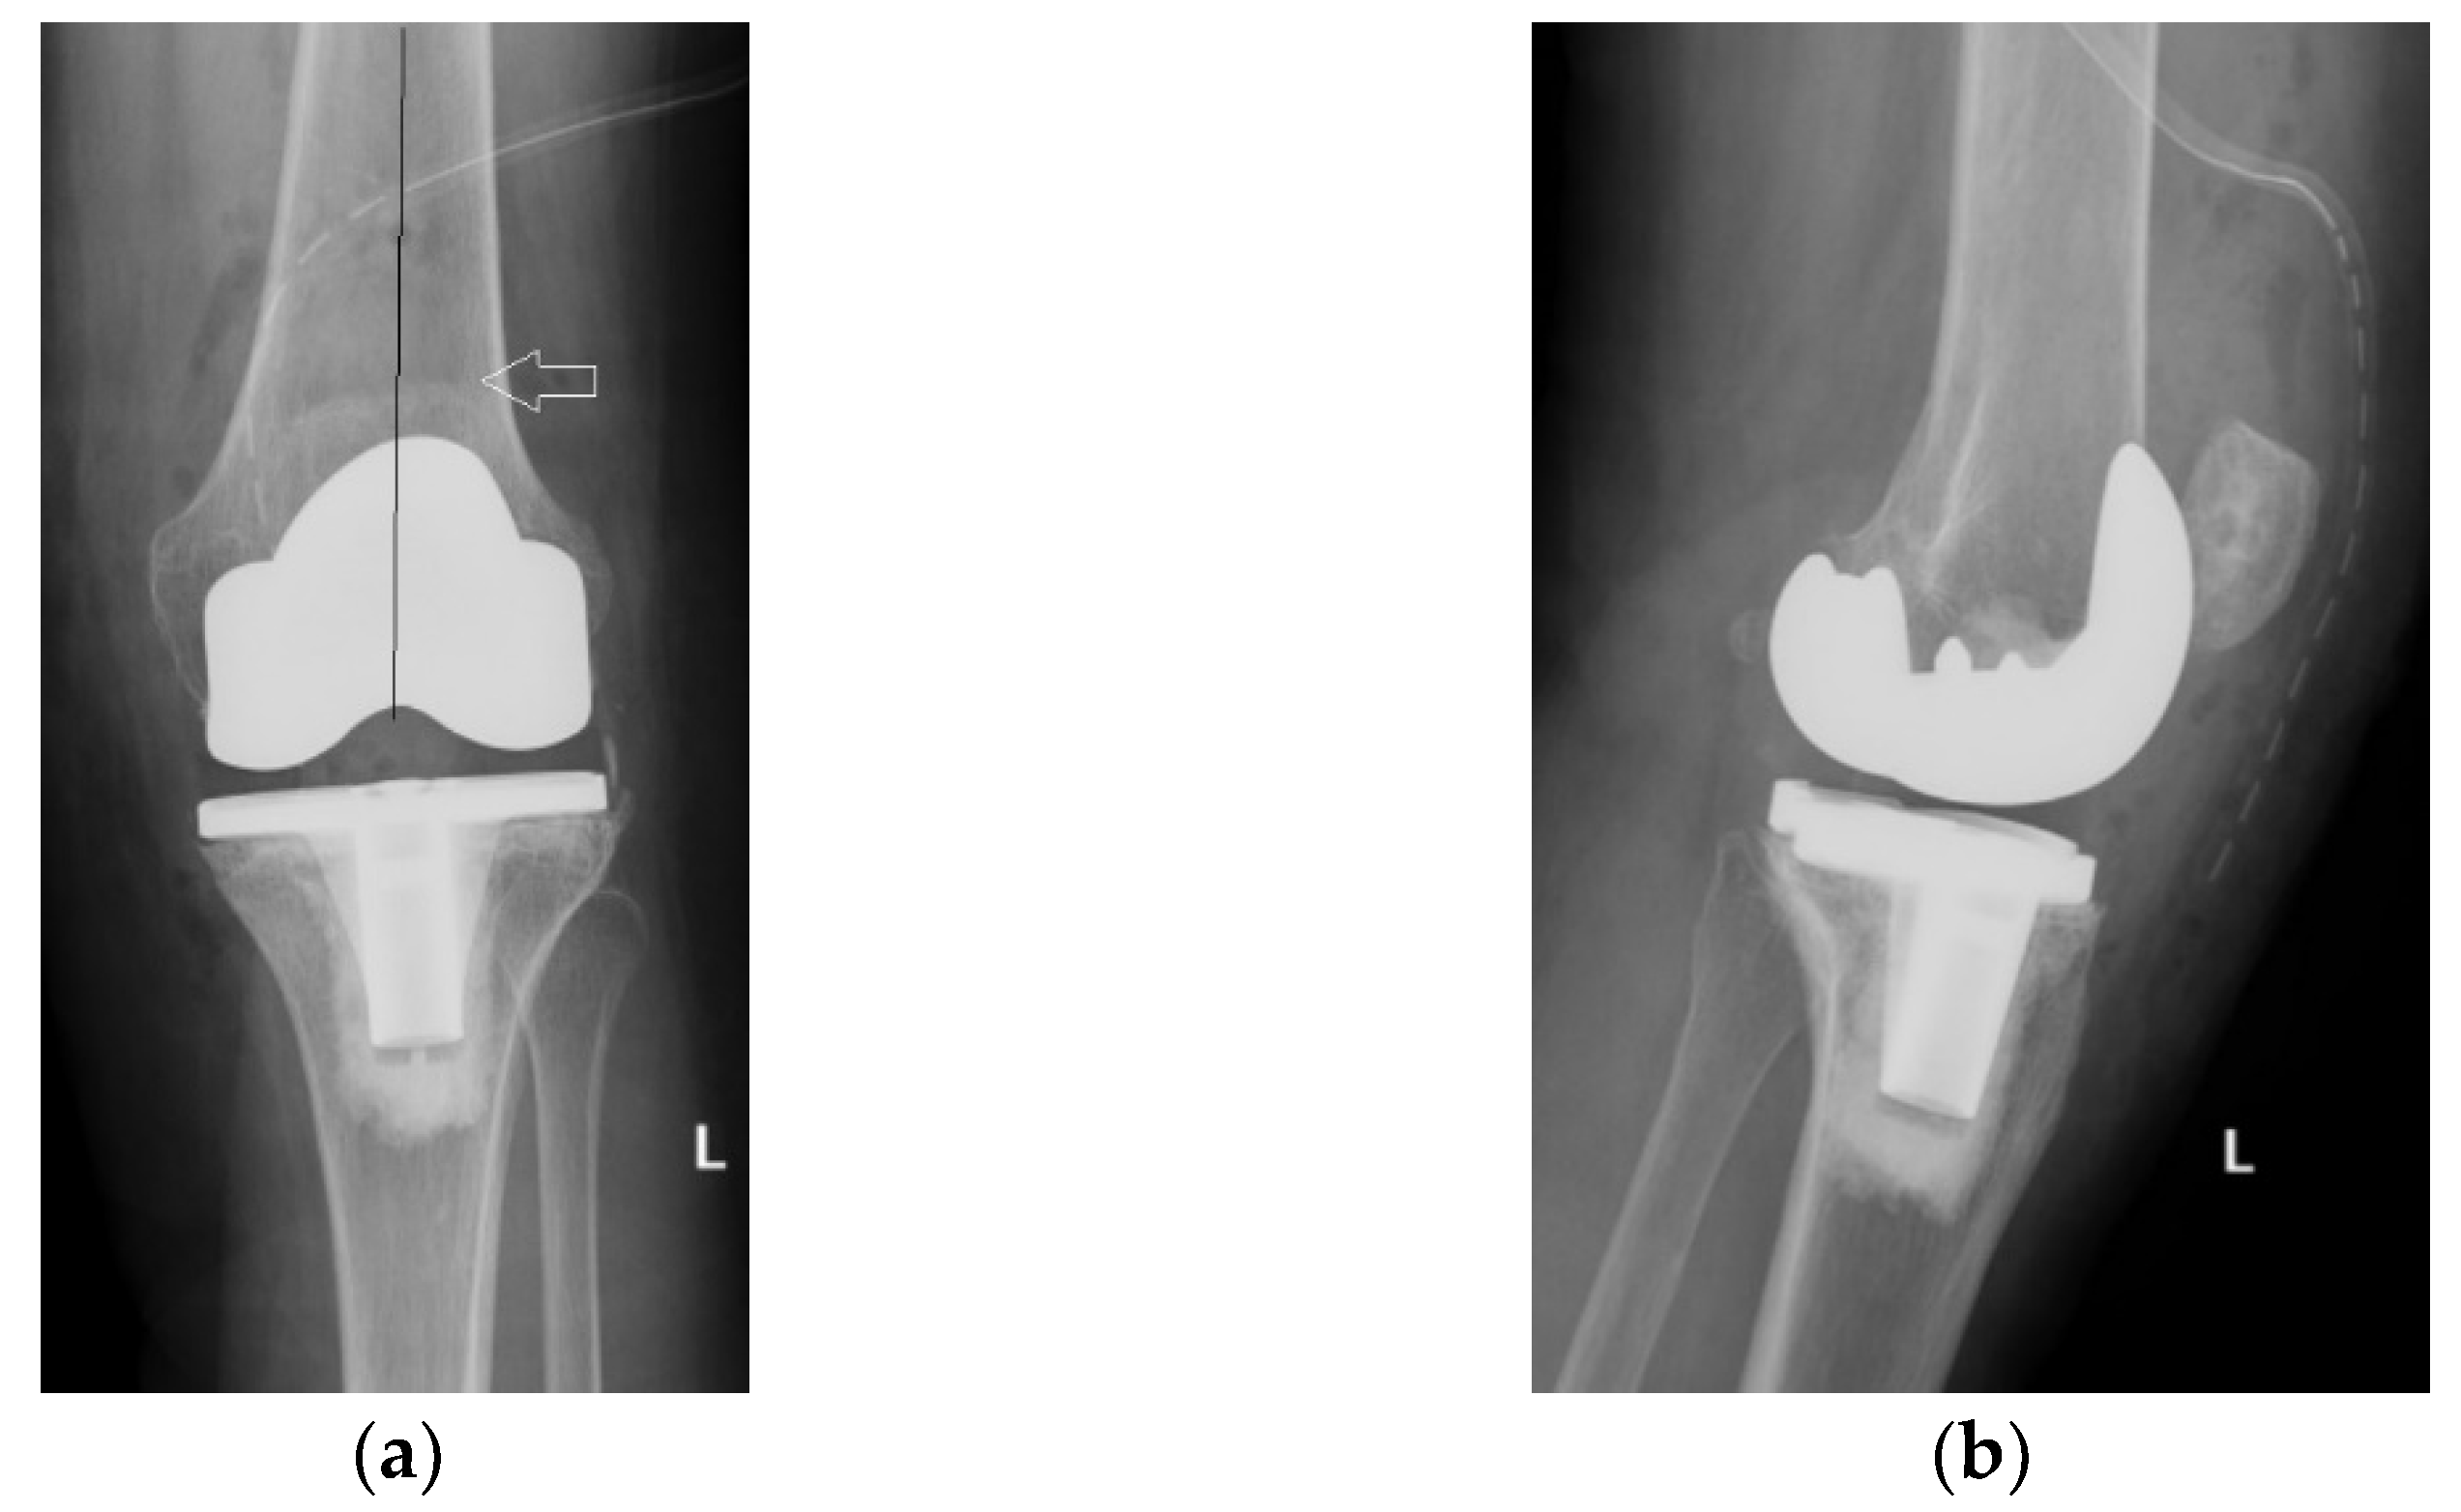

Four years ago, the patient was diagnosed with Ahlback stage IV gonarthrosis and underwent a simultaneous bilateral TKA surgery in another orthopedic clinic. Two NexGen cemented total prostheses were then implanted, with patellar resurfacing performed only on the right side, due to anesthetic complications which required a drastic shortening of the operating time, thus preventing the surgical team from performing resurfacing on the contralateral patella. Although postoperative radiological images showed a slight implantation error in the femoral component on the right side, extensive anterior resection with posterior rotation of the femoral component, the clinical outcome was satisfactory (Figure 1).

Figure 1.

Right knee, initial after surgery radiological image: (a) lateral view, extensive anterior resection, femoral posterior rotation, femoral component axis intersecting diaphyseal axis at a 15.4° angle with (1) marking the femoral diaphyseal axis and (2) marking femoral component rotation axis; (b) coronal view.

On the other hand, on the left side, where patellar resurfacing was not performed, although the radiological images show a satisfactory implantation of the prosthesis with correct alignment of the tibial and femoral components, but with slight subluxation of the patella, the clinical evolution was unsatisfactory (Figure 2). Shortly after operation, 3–4 weeks, the patient experienced discomfort, pain and swelling of the left knee.

Figure 2.

Initial radiological aspect of the left knee, right after surgery: (a) lateral view, femoral component axis parallel with femoral diaphyseal axis; (b) coronal view, slight lateral patellar subluxation (arrow) compared to femoral axis with (1) marking the femoral trochlear axis, (2) the patellar axis, and (3) patella must be centered in the femoral trochlea.